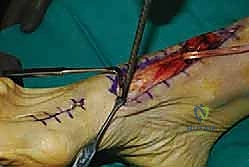

Clinical & Radiographic Imaging